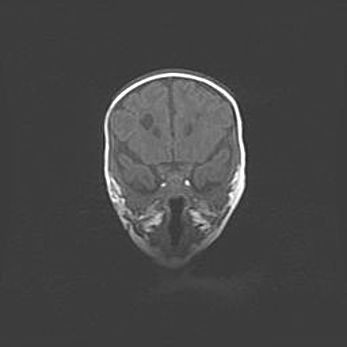

Неполная лизэнцефалия (пахигирия). Открытая гидроцефалия.

Возраст: 17 дней

Вес: 3110 г

Пол: мужской

Окружность головы: 33,5 см

Срок гестации: 35-36 недель

Лизэнцефалия—недоразвитие корковой пластинки и мозговых извилин в результате нарушения миграции нейронов коры. Поверхность мозговых полушарий гладкая. Микроскопически выявляется отсутствие нормальных слоев коры и скопление групп нейронов в подкорковом белом веществе.

Пахигирия—уменьшение числа вторичных извилин. В пораженном полушарии нервные клетки образуют толстый недифференцированный слой с неправильно расположенными нервными волокнами и группами гетеротопных клеток. Нервные клетки незрелые. Белое вещество истончено. При этом нередко аномально развит корково-спинномозговой путь.